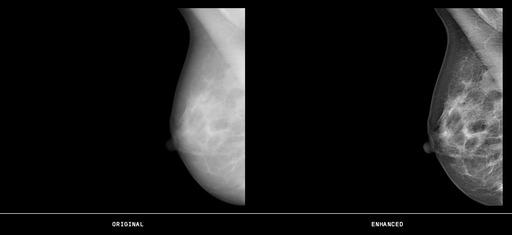

November 25, 2013 — ContextVision will introduce GOPView Mammo2 features at the Radiological Society of North America Annual Meeting (RSNA 2013). The GOPView provides high digital mammography image quality software for medical imaging manufacturers. Using ContextVision’s GOP technology in combination with optimized mammography algorithms, GOPView Mammo2 makes it easier for clinicians to quickly diagnose patients. The advanced imaging proves especially valuable in dense tissue with high contrast, providing a sense of depth, more rapid and accurate diagnoses and a greater return-on-investment for medical imaging users worldwide.

GOPView Mammo2, the latest upgrade to ContextVision’s mammography product line, includes several new features that will improve clinicians’ abilities to properly diagnose patients. These features include:

• Great contrast within the parenchyma, which provides efficient visibility of lesions and subtle structures

• Efficient noise suppression balanced with a strengthening of edges and fine structures all the way out to the skin line

• New segmentation that provides clear and natural skin line and mammilla

• Optimized display adapted for each image

• Optimized contrast between pectoral muscle, fat and parenchyma